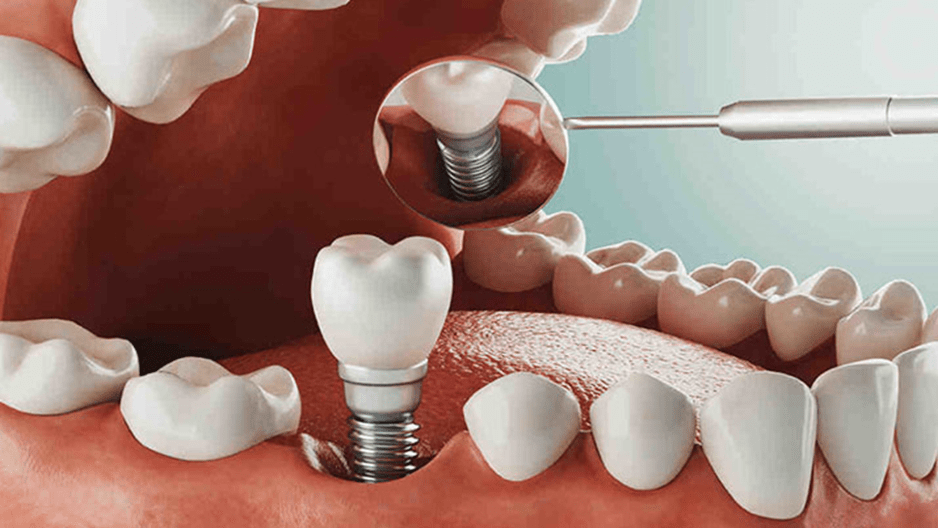

ایمپلنت پانچ یا ایمپلنت بدون جراحی که با نامهای ایمپلنت یک روزه، ایمپلنت فوری یا ایمپلنت فلپلس نیز شناخته میشود یکی از کارآمدترین شیوهها برای جایگزینی دندانهای از دست رفته است که میتوان آن را حاصل پیشرفت علم دندانپزشکی دانست. از آنجایی که در این روش، کاشت دندان بدون جراحی و شکاف لثه صورت میپذیرد، میتوان آن را روشی کم تهاجم و بدون درد برشمرد که بسیاری از افراد مایل به انجام آن هستند.

مراحل انجام ایمپلنت به روش پانچ

اگر برای انجام ایمپلنت به روش پانچ به کلینیک دندانپزشکی زیبایی مراجعه کنید، در ابتدا دندانپزشک با استفاده از تصاویر سه بعدی رادیوگرافی ساختار استخوان، لثه و دندانهای شما را به طور دقیق و کامل مورد بررسی قرار میدهد تا در صورت اطمینان از وجود استخوان فک به میزان کافی، نرمی لثه و عدم عفونت و پلاک، اقدام به انجام ایمپلنت بدون درد و جراحی نماید.

در صورت وجود شرایط ذکر شده، دندانپزشک به کمک بیحسی موضعی دهان و لثه بیمار را بیحس کرده و با دستگاههای مخصوص پانچ که سرهایی با اندازههای متفاوت دارند، سوراخهایی را با عمق لازم برای کاشت دندان ایجاد مینماید تا پایههای ایمپلنت دندان از جنس تیتانیوم را درون لثه قرار دهد. در انتها نیز توسط دستگاههای خاص سوراخهایی که برای نصب ایمپلنت به روش پانچ ایجاد شده بود، ترمیم میشوند. همین امر موجب میگردد تا به دلیل عدم جراحی و باز شدن لثه، زمان جوش خوردن استخوان فک به پایه ایمپلنت کوتاهتر شده و روند بهبودی سریعتر طی شود.